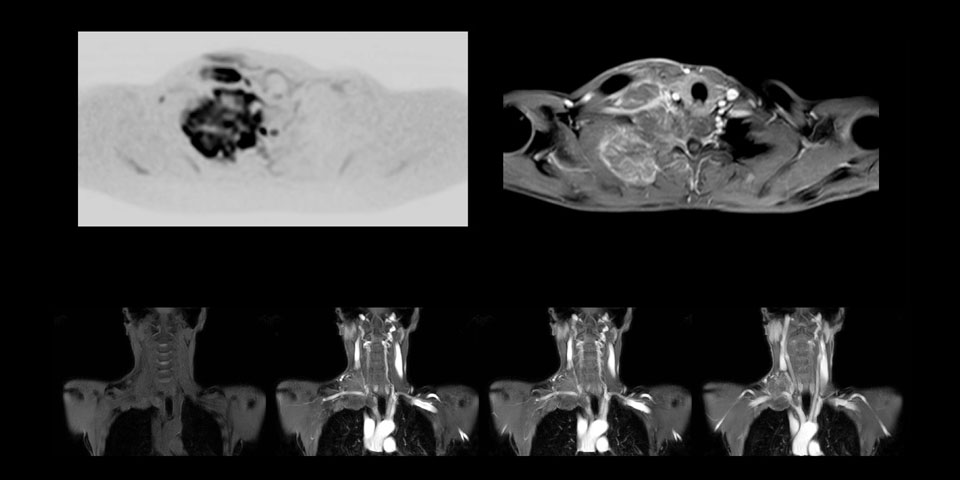

Whole body diffusion

A 61-year-old female with a malignant lymphoma underwent an MRI exam with whole body diffusion weighted imaging (DWIBS) as well as PET. On the images shown, the resolution of DWIBS is better than PET, which allows visualization of the small pelvic lesions and almost no distortion is seen in the neck area.

This patient is a 43-year-old female with a left supraclavicular nerve sheath tumor. The lesion is well visualized on the STIR VISTA images and on the MR neurography using DWIBS. The exam was performed on Prodiva 1.5T.

MR neurography using DWIBS inverted, full MIP

Acq voxel size 1.2 x 1.3 x 2.4 mm, Recon voxel size 0.7 x 0.7 x 1.2 mm, dS SENSE factor 2, scan time 5:46 min.